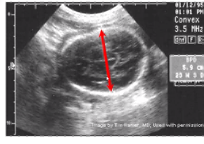

Obstetric ultrasound scan (USS)

Estimation of fetal age based on 2 factors

estimation of fetal age in trimester 1

Crown rump length

estimation of fetal age in the 2 and 3 trimester

Biparietal diameter

Abdominal cirucmferene and femur length

3- or 4-D USS

Great at detecting potential congenital anomalies